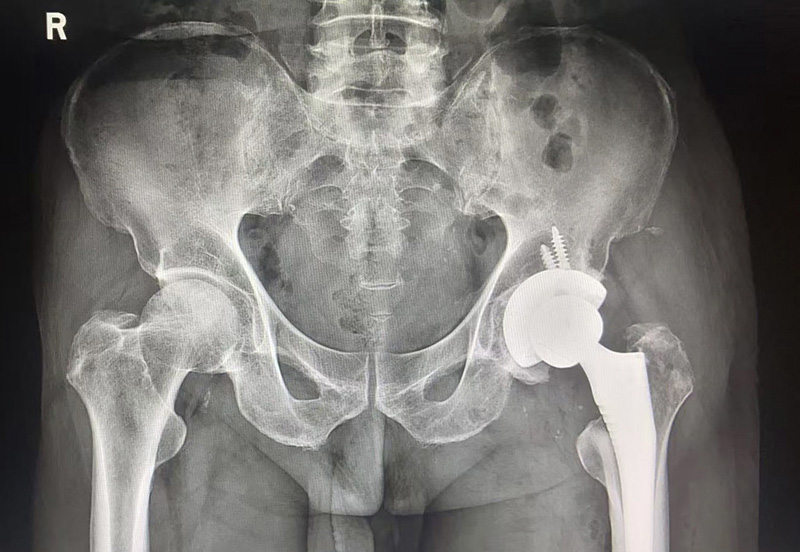

2025-11-14近日,骨科在麻醉科的协助下,成功完成我院首例左股骨头缺血性坏死全髋关节置换术。患者为中年男性,四年前出现双髋部疼痛,以左侧为著,行走约300米后疼痛即加重。曾在当地医院就诊,对症治疗效果不佳,于11月3日来到我院就诊并接受治疗。

在排除手术禁忌症后,于11月7日李李连亭主任亲自为患者施行左侧全髋关节置换术。整个手术过程顺利,术中出血量少,患者术后恢复迅速。